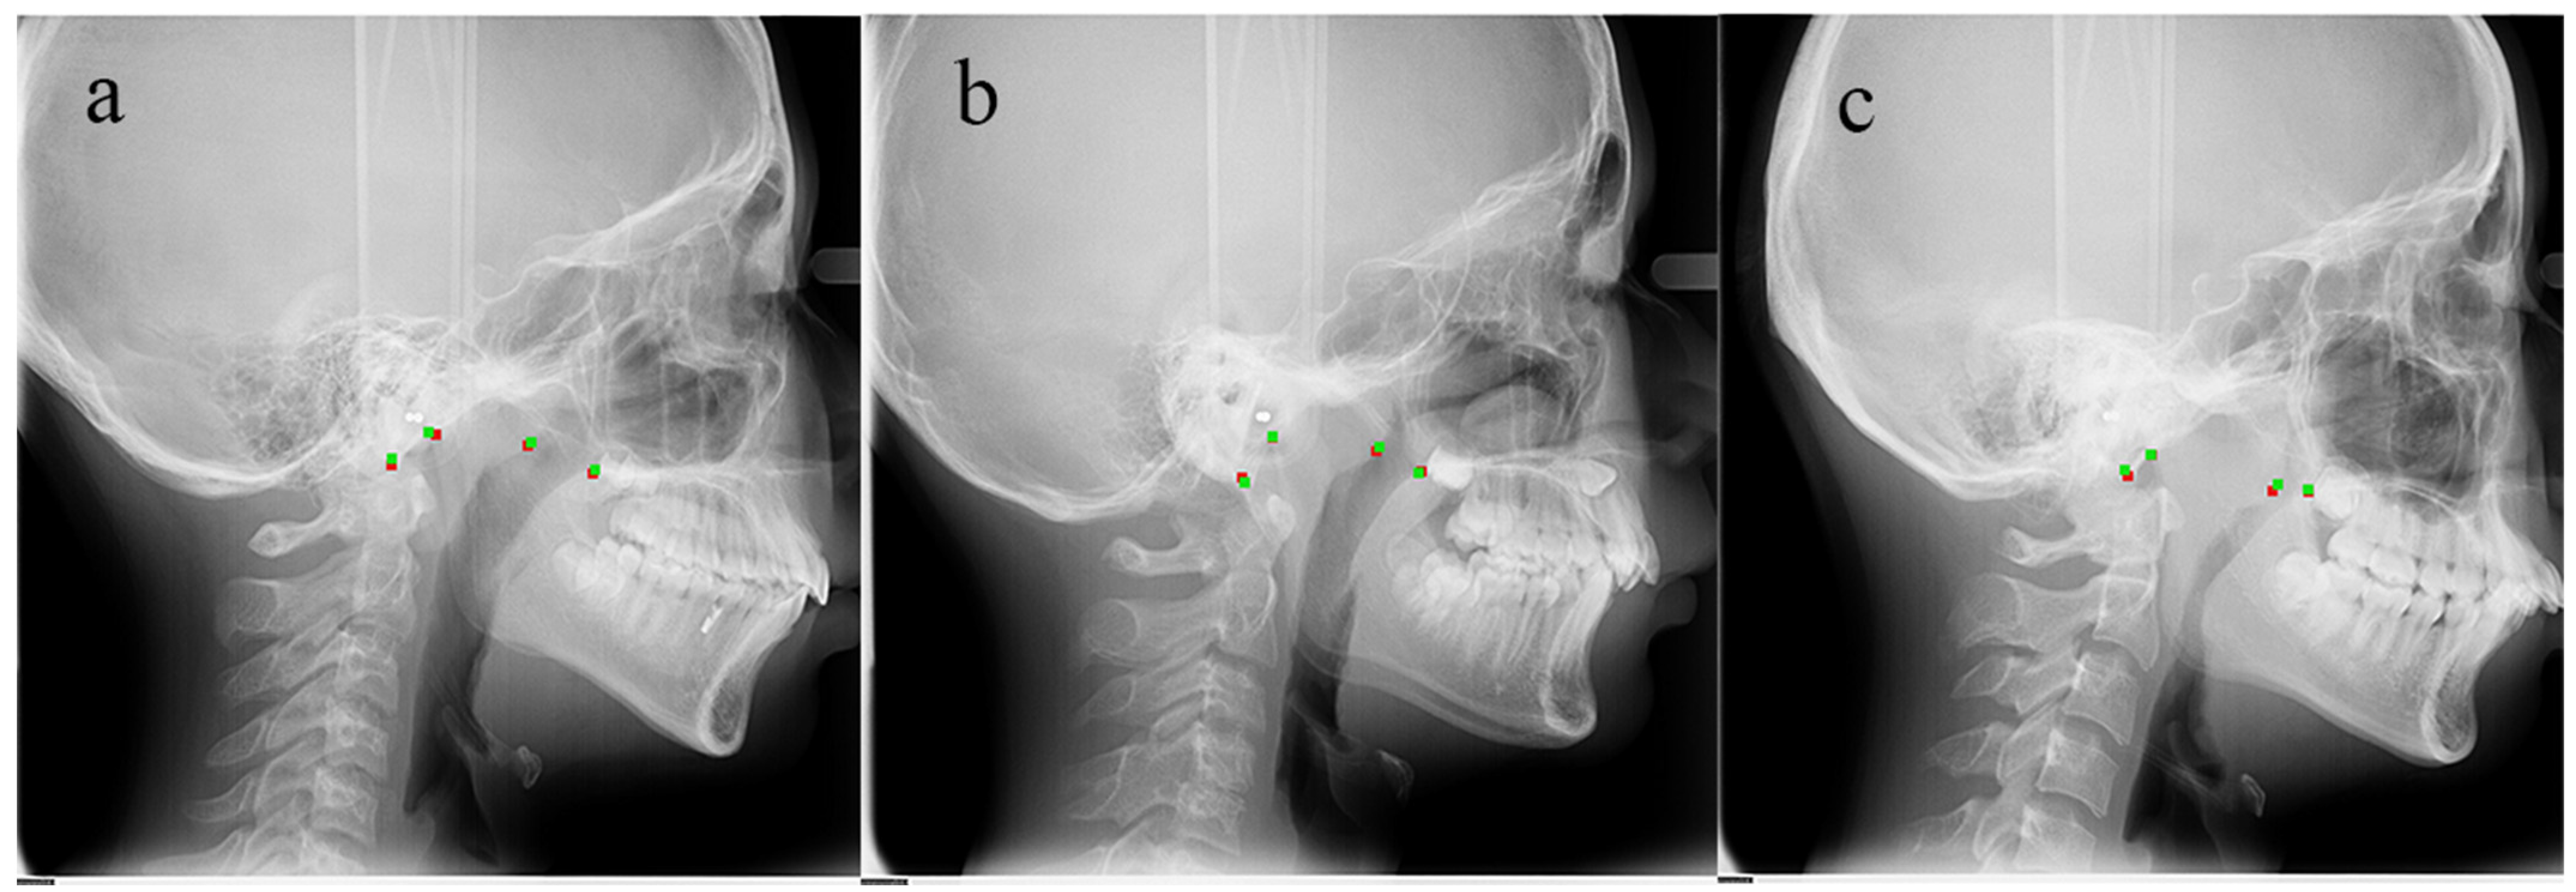

2.1. Samples and Identification of Landmarks